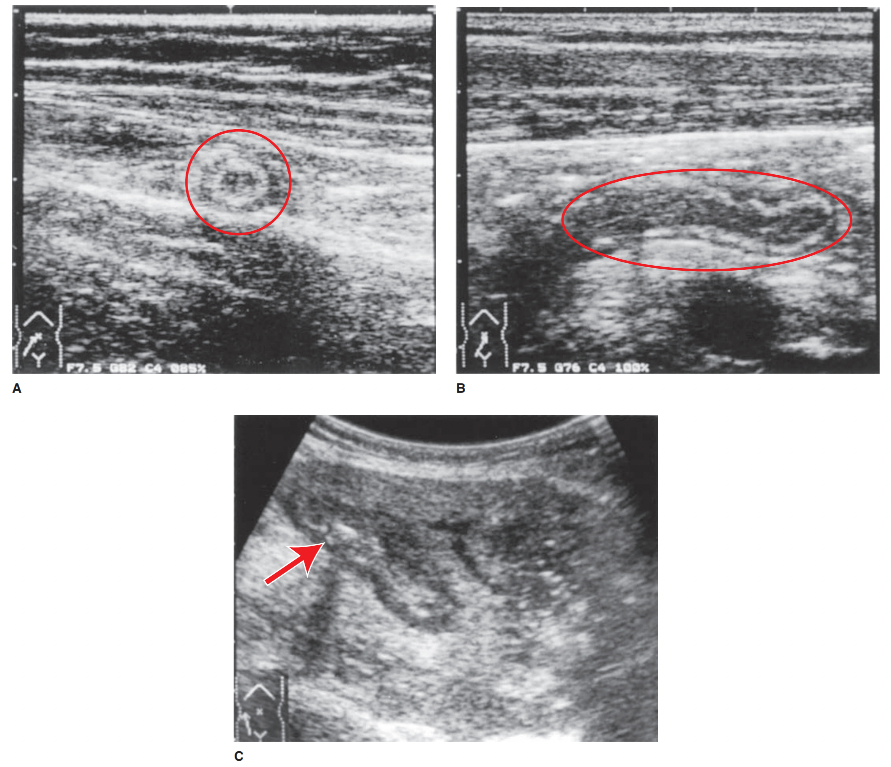

“Should be the initial imaging modality of choice in both pregnant females and children.”

A

Graded compression ultrasound

- it should be likewise be considered in young, nonobese adults

- typical findings in appendicitis are a thickened, noncompressible appendix >6 mm in diameter

- perforation may lead to disappearance of specific imaging hallmarks and difficult visualization of the appendix on US